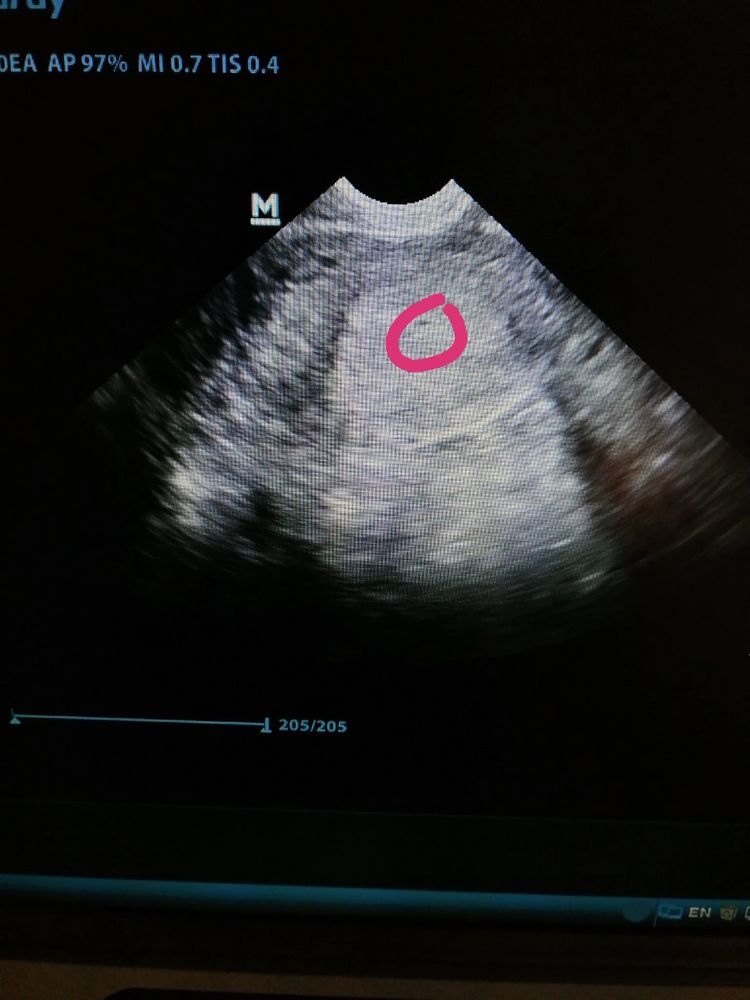

Плодное яйцо ,сгусток

Плодное яйцо 2 мм

Я пришла в ЖК и мне сказали что это врач тупой он типо слишком приблизил увеличил и что это просто был какой то сгусток а он перепутал его с плодным яйцом

Тогда я ничего не стала делать я просто поняла хорошо я не беременна, и потом у меня пошли месячные через какое то время, и все я забыла об этом , но сейчас когда я планирую я наткнулась на это узи и думаю что это все таки тогда было, может быть какая то замершая беременность